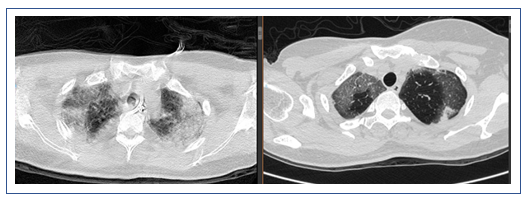

2019年1月16日复查胸部CT:双侧中下肺实变影较1月9日增多(图7)。

图7 患者复查胸部CT与前对比

左:2019年1月16日CT;右:2019年1月9日CT

患者1月4-6日使用激素,然后停用,胸部CT显示部分病变加重,部分病变被吸收;另外,中下肺背部实变比较明显,而且气管和支气管征比较突出,另外,病变沿着气管、支气管束的分布,符合机化性肺炎表现。但是机化性肺炎不能引起类似呼吸衰竭如此严重的情况,所以个人考虑是否为纤维素性机化性肺炎(AFOP),当然需要病理诊断来进一步明确。患者淋巴细胞非常低,这是目前很难解释的,所以还是期待进一步的检查。

该患者的实变处于整个重力依赖区,从双上肺的后段到下面的背段。一方面可能是停用激素后的反弹,另外一方面考虑跨肺压过小,与长期仰卧位机械通气有关,另外,PEEP过高对患者也有不良影响。此类患者如果不用激素,可以考虑俯卧位通气,能够短期迅速缓解患者重力依赖区的实变。我们还是期待后续的检查结果。